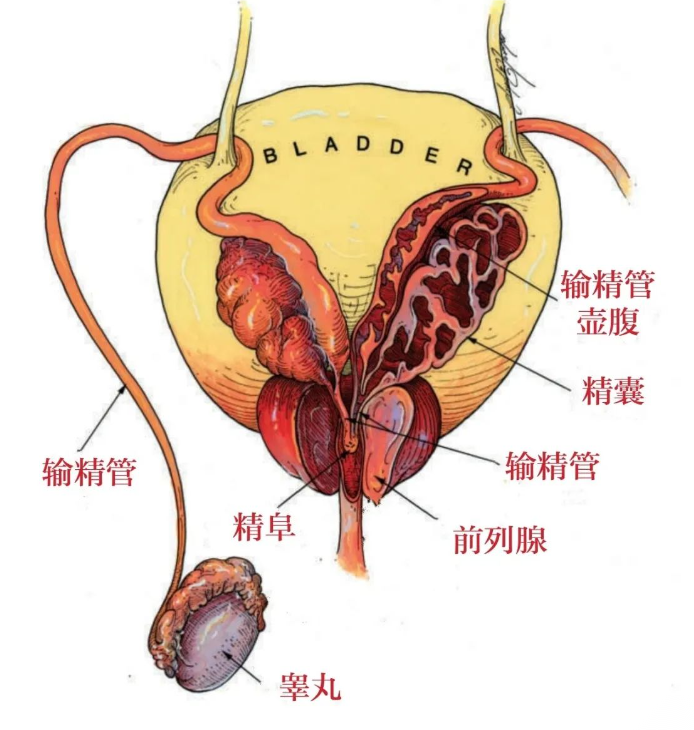

血精发作时,精液由正常时的灰白色突然变成红褐色、粉红色或混有血丝,当然是混进了血液所致,其颜色变化取决于出血时间的早晚,如果是新鲜出血,精液颜色可呈鲜红色,出血量多时整份精液会完全呈血性,而且会形成凝血块;如果排精间隔时间过长,血液积存在精囊内时间久了,血液中的铁经过氧化则呈铁锈色;如果出血量较少,而且为单侧精囊出血,可能精液中仅仅混有少许血丝;如果长期反复血精,精囊内大量沉积的血块会机化,慢慢形成结石。临床上血精这种症状并不少见,大约占泌尿外科所有症状的1%左右,常见于20-50岁性活动较活跃的青壮年 。

引起血精的主要原因是泌尿生殖道炎症、梗阻和结石,占血精患者的比例2/3。泌尿生殖系感染包括附睾炎、附睾睾丸炎、尿道炎、前列腺炎、精囊炎,其中以精囊炎和前列腺炎最为常见。对于50岁以上的血精男性应排除泌尿生殖系统癌症。除此之外,全身出血性疾病、盆腔局部的外伤、手术、穿刺也是血精的病因。